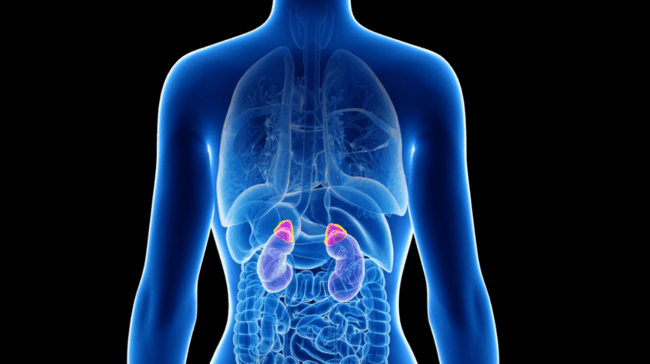

Adrenal Gland Diseases

What are Adrenal Gland Diseases? Adrenal Gland Diseases | The adrenal glands (adrenal glands) are small, triangular-shaped organs located on top of each kidney in the body. These glands play a critical role in regulating the body’s hormonal balance. The adrenal glands consist of two main sections: the adrenal cortex (outer part) and the adrenal…